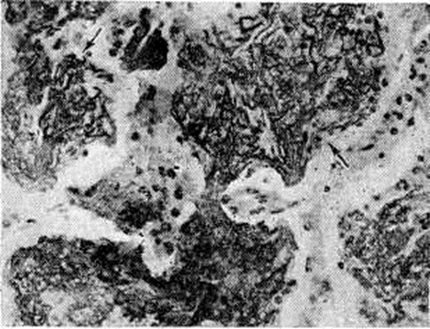

Для Пневмония при острых вирусных респираторных инфекциях (гриппе, парагриппе, респираторно-синцитиальной и аденовирусной) наиболее характерно поражение эпителия слизистой оболочки дыхательных путей и альвеолоцитов. В результате внутриклеточного размножения вирусов происходит повреждение этих клеток с развитием дистрофических и некротических изменений. При благоприятном течении заболевания через несколько дней в них возникают реактивные изменения в виде уплотнения цитоплазмы вокруг участка повреждения — фуксинофильные включения) (рисунок 3, б). Наряду с этим наблюдаются умеренно выраженные воспалительные изменения слизистой оболочки дыхательных путей с преобладанием нарушений кровообращения в виде полнокровия сосудов, выпотевания серозной жидкости в просвет альвеол и небольших кровоизлияний. Отмечаются также небольшие скопления нейтрофильных лейкоцитов и альвеолярных макрофагов. В результате нарушения образования сурфактанта (смотри полный свод знаний) возникают небольшие ателектазы (смотри полный свод знаний), большей частью неполные,— дистелектазы (рисунок 3, в), что особенно выражено у детей раннего возраста, а также компенсаторное очаговое расширение альвеол в других участках лёгких. Макроскопические изменения при этом незначительны и заключаются в основном в катаральном воспалении дыхательных путей и образовании в лёгких небольших участков уплотнения темно-красного или синюшного цвета. Наиболее характерной чертой вирусной Пневмония является гигантоклеточное превращение поражённых эпителиоцитов.

При гриппе поражённые клетки несколько увеличиваются в объёме, в случае же отторжения превращаются в крупные одноядерные клетки, значительно превышающие по размерам обычные альвеолярные макрофаги (рисунок 3, г). Для парагриппа типичны подушкообразные разрастания, сосочковидные выросты слизистой оболочки. При респираторно-синцитиальной инфекции они ещё более выражены. При аденовирусной Пневмония происходит образование крупных одноядерных клеток (гигантоклеточный метаморфоз альвеолоцитов), а также выраженное накопление экссудата (рисунок 3, д). При выздоровлении происходит регенерация эпителия дыхательных путей. Вначале выявляются недифференцированные уплощённые эпителиальные клетки, располагающиеся обычно в несколько рядов (рисунок 3, е), которые в дальнейшем дифференцируются .

Изменения, сходные с морфологический изменениями при вирусной Пневмония, наблюдаются при микоплазменной Пневмония — респираторном микоплазмозе (смотри полный свод знаний Микоплазменные инфекции). Для неё также типично внутриклеточное размножение возбудителя (рисунок 4), хотя возможно и внеклеточное. Поражения носят характер десквамативной Пневмония при весьма умеренных макроскопических изменениях (цветной рисунок 3—5; 6—10).